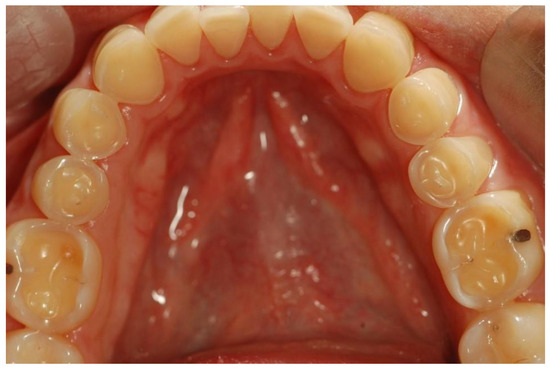

4.4. Dental Health

4.4.1. Dental Caries

4.4.2. Erosive Tooth Wear